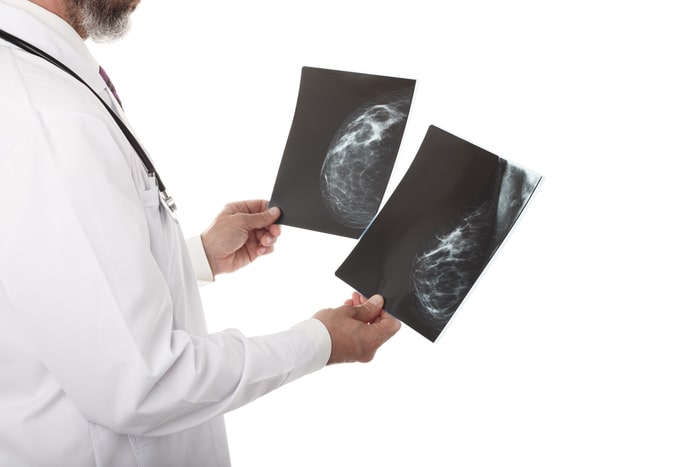

O carcinoma lobular é o segundo tipo de carcinoma de mama mais comum em mulheres, correspondendo a 15% dos casos. Ele é uma metaplasia que acontece nos lóbulos. Normalmente possui uma maior dificuldade de ser detectado pela mamografia. Ele também pode ser dividido em dois tipos, como veremos a seguir

O carcinoma lobular in situ é bem menos comum e costuma não aparecer na mamografia. Alguns especialistas não o consideram como um câncer, preferindo identificá-lo como uma neoplasia lobular, que é considerado, também, como uma lesão precursora do câncer de mama, que pode aumentar em quatro vezes o risco de câncer de mama. Os tratamentos podem ser diversos, de acordo com a situação, podendo estar entre eles:

O carcinoma lobular invasor também possui baixa detecção na mamografia, e também pode ser encontrado em vários focos na mama. Além disso, ele também tem como característica ter resistência à quimioterapia.

Importância do diagnóstico precoce do carcinoma

Como você viu ao longo deste artigo, o sucesso do tratamento do carcinoma depende diretamente de um diagnóstico precoce. Isso porque alguns tumores evoluem rapidamente e, assim, as chances de metástase são altas. Contudo, quando descobertos precocemente, podem ter chances de cura de mais de 90%.